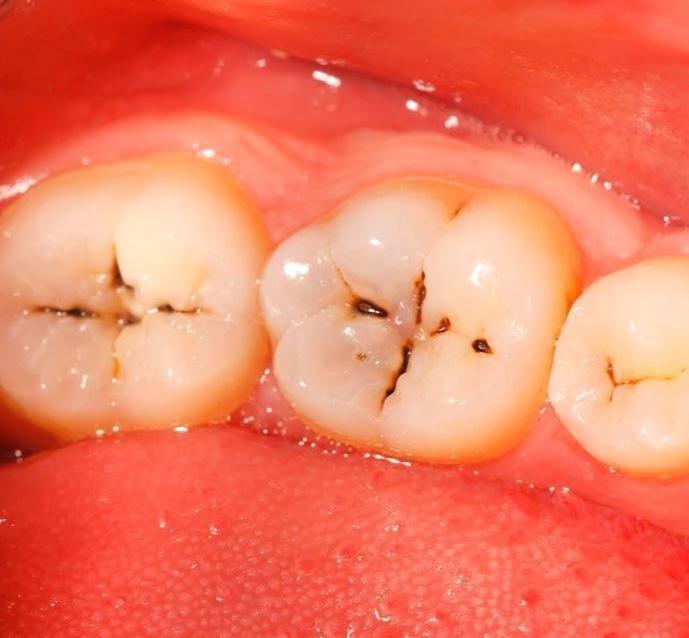

这是一种龋齿,窝沟龋。

龋齿按不同的牙齿部位可以分为窝沟龋和平滑面龋。

我们的前磨牙和磨牙咬合面是窝状的,上面有很多沟隙,它们被称为“窝沟”。这种窝沟可以使口腔咬合面凹凸不平,增大咀嚼面积,提高咀嚼效率。

但这个窝沟有一个缺点,那就是容易使食物、菌斑停留在这里,并且不易清洁,因此窝沟是龋齿最容易发生的部位。

窝沟龋早期的表现就是后牙咬合面有黑线

但如果不加以重视龋坏会扩散,就会沿着釉柱方向发展而加深,达到牙本质而形成一个口小底大的三角形,然后沿牙本质界扩散。

另外,由于釉质在窝沟底部牙厚度较薄,窝沟龋很容易进展到牙本质,造成大面积的牙齿病变,所以窝沟龋病程发展很快,程度也会比其他口腔疾病更严重。除此之外,细菌还可以通过牙本质小管到达牙髓腔,引发炎症。